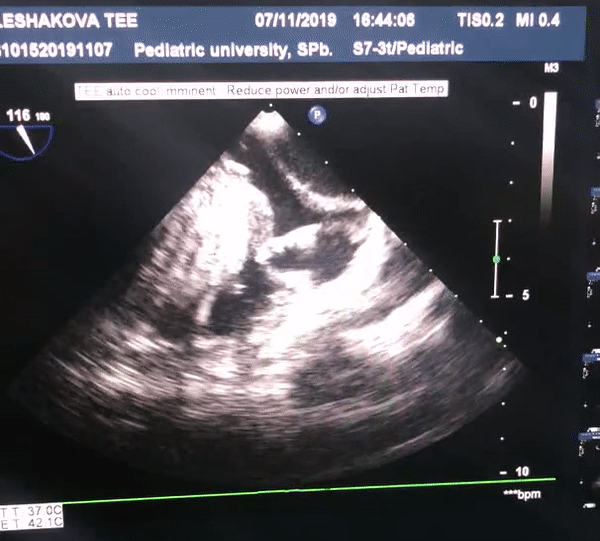

Выполняется трансторакольное ЭХОКГ исследование, которое позволяет заподозрить локализацию и размер опухоли, ее соотношение с другими анатомическими структурами сердца.